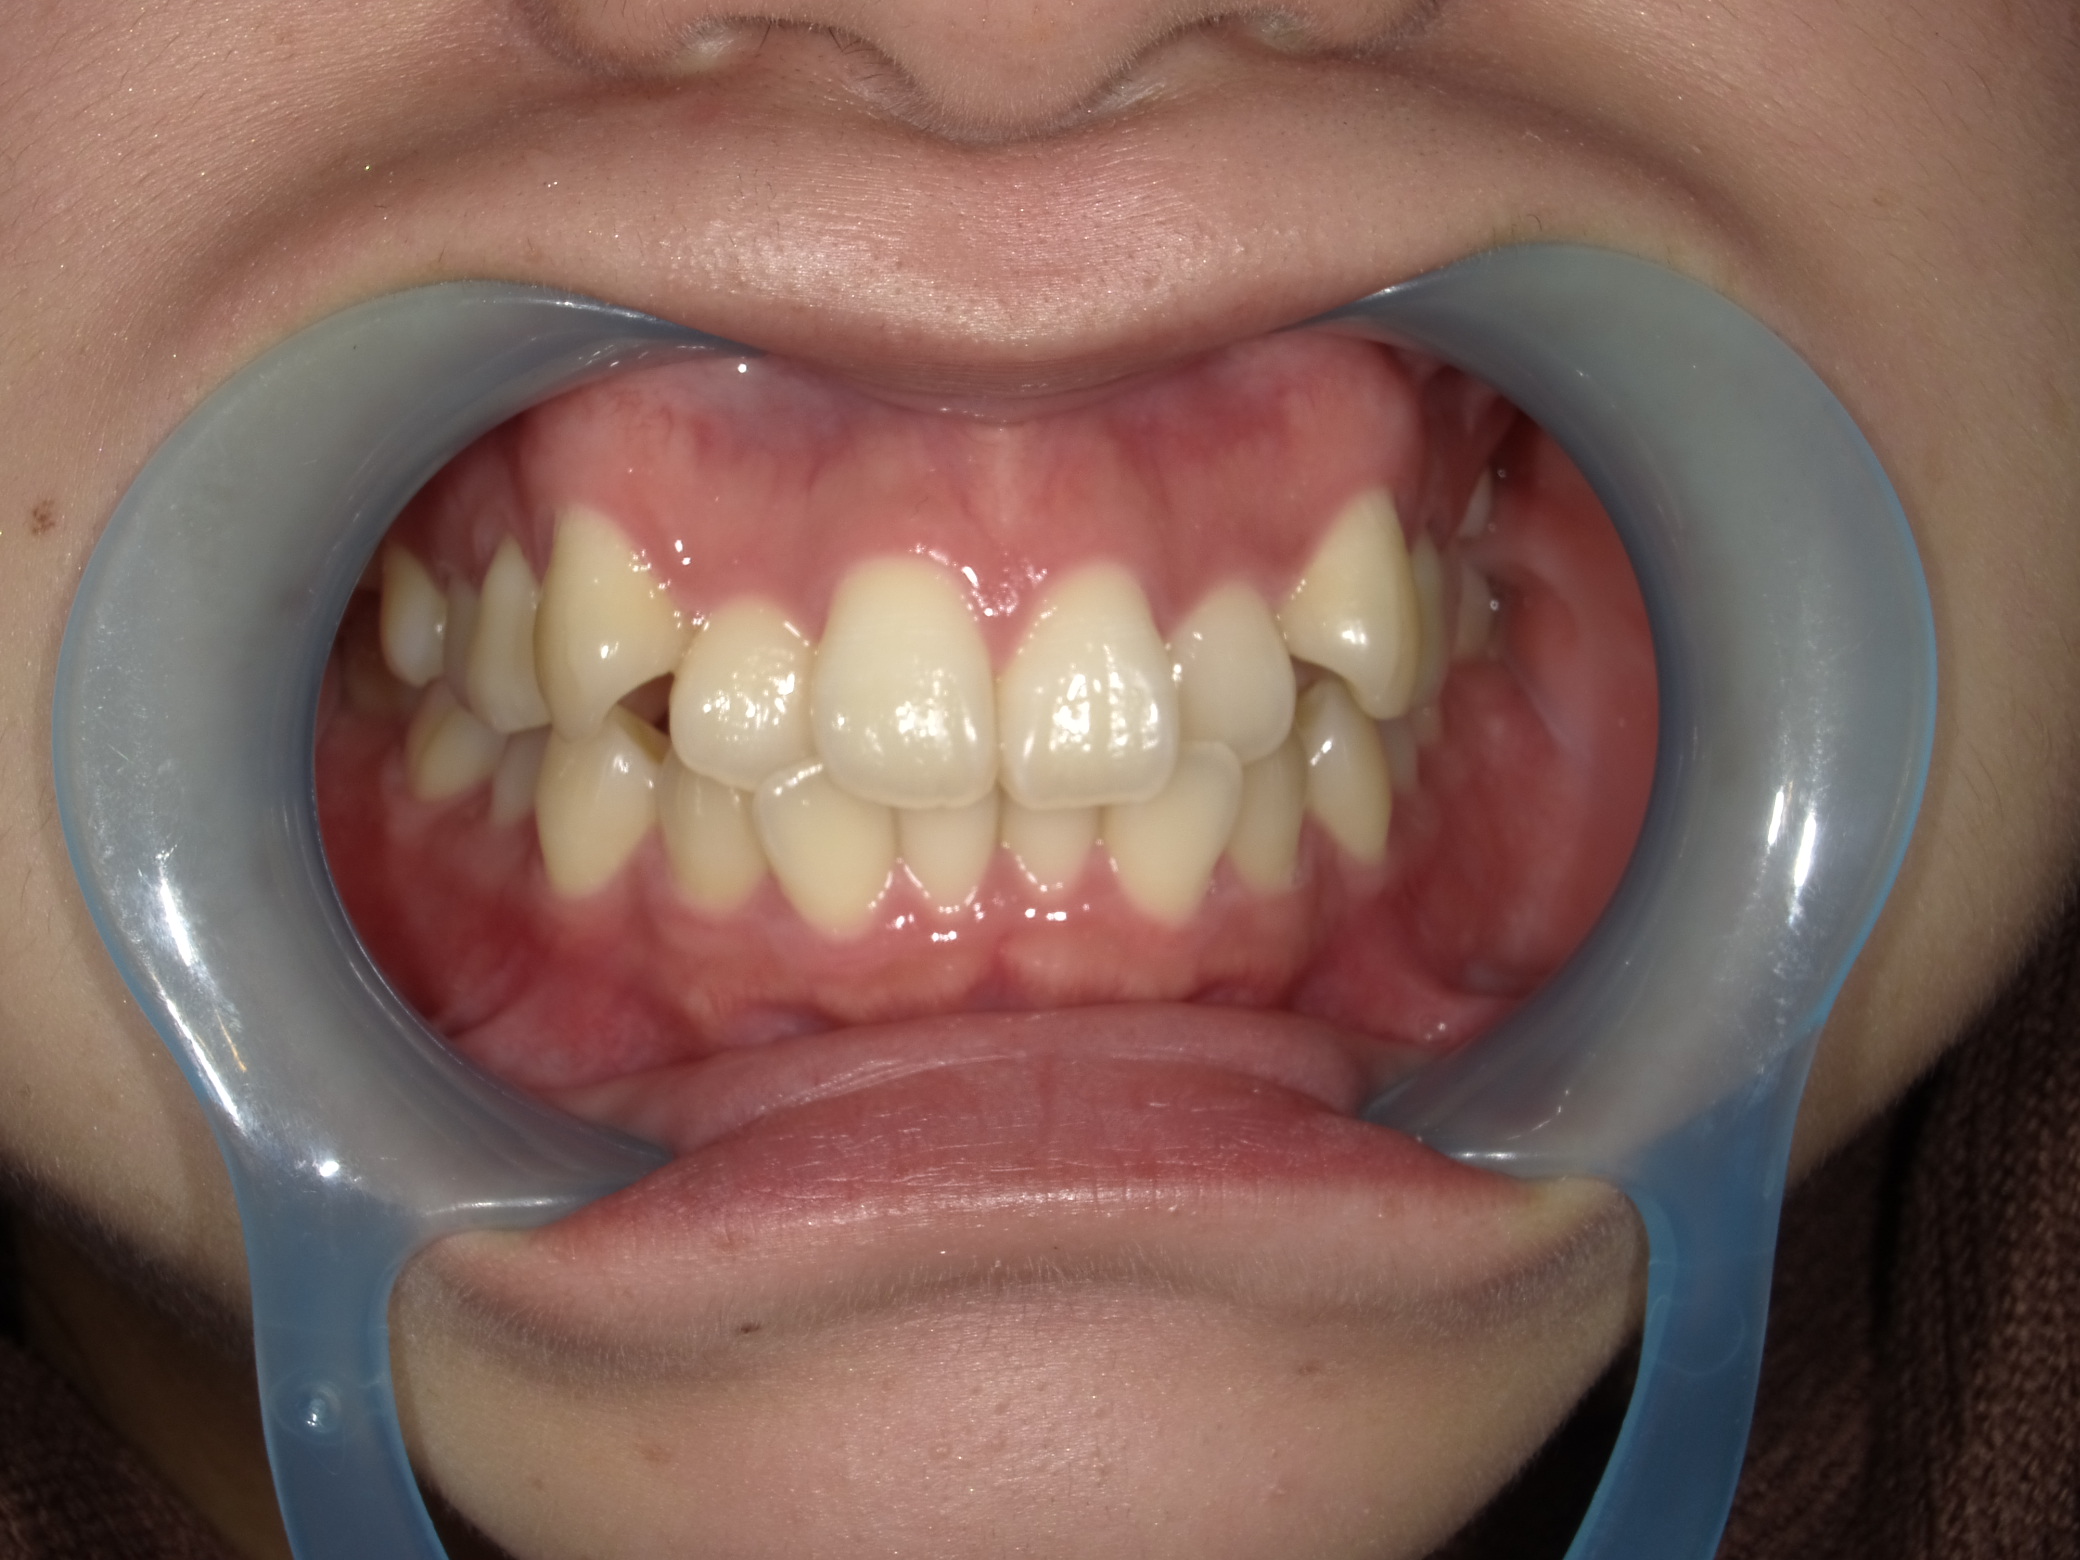

◾️治療前の状態(Before)

上顎前歯部に八重歯(叢生)が見られ、犬歯が歯列から外側に突出している状態。

◾️治療後の状態(After)

インビザライン矯正により前歯部の歯の重なりが解消され、犬歯を含む前歯が歯列内に収まりました。

前歯の突出感(出っ歯の印象)も軽減され、全体として自然で違和感の少ない歯並びに仕上がった症例です。

◾️治療内容の概要

治療方法:マウスピース型矯正装置(インビザライン)

治療期間:6ヶ月

◾️矯正治療に伴うリスク・注意点

歯列矯正中に伴う疼痛・咬合痛・う蝕・歯肉退縮などのリスクがあります。治療期間や費用については個人差があります。